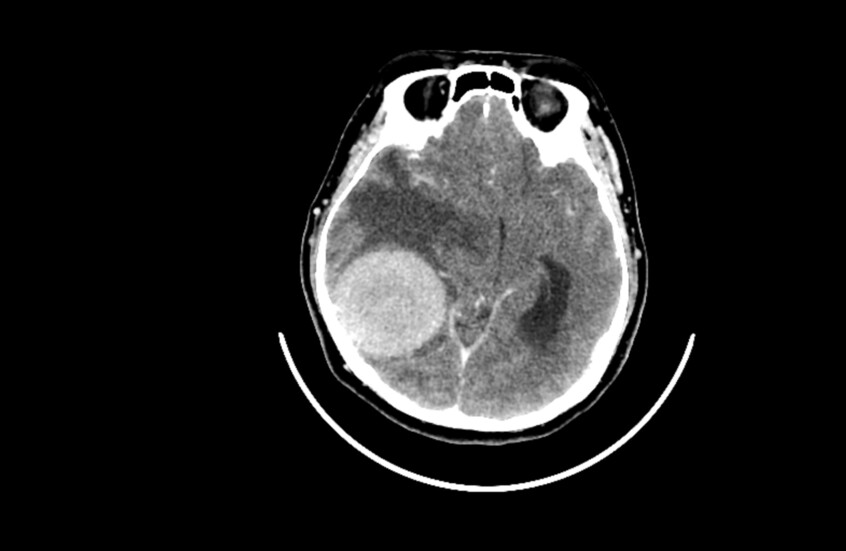

دراسة صادمة .. القلق والدوار يرتبطان بأورام الدماغ!

عمون - توصلت دراسة حديثة إلى وجود علاقة بين القلق والدوخة من جهة، والأورام الدماغية الحميدة من جهة أخرى.

ويرتبط الورم الشفاني الدهليزي، أو كما يعرف أيضا باسم ورم العصب السمعي (وهو ورم حميد يصيب العصب المسؤول عن السمع والتوازن وينمو ببطء)، عادة بأعراض مثل فقدان السمع والطنين والدوار. لكن الدراسة الجديدة تكشف أن للعوامل النفسية دورا محوريا في شدة هذه الأعراض.